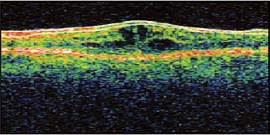

A 74 year-old male with a 15 year history of non-insulin-dependent diabetes presented for a routine cataract procedure. There were no intraoperative complications and he did very well post-procedure. At the time of his 1-month postoperative exam, his vision had declined to 20/70. Optical coherence tomography (OCT) revealed classic cystoid macular edema (CME).

The patient was treated with prednisolone acetate and ketorolac tromethamine 0.4% (Acular LS, Allergan) q.i.d. He returned in 4 weeks, at which time his vision had improved to 20/25. He was instructed to taper his medications. However, he discontinued them on his own when he felt that his vision had recovered to its baseline. Three weeks later, the patient returned emergently, as the CME had recurred and his vision had decreased to 20/60. He was placed again on 1% prednisolone and ketorolac 0.4% q.i.d., returning 4 weeks later showing no evidence of CME on OCT, with 20/20 visual acuity (VA).

Figure 1. Typical cystic spaces confirming the diagnosis of CME (abnormal).